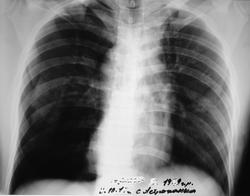

Мужчина 34 лет, травмирован в результате ДТП. Двухсторонние множественные переломы ребер. Гемопневмоторакс справа, пневмоторакс слева. Перелом правого бедра. Первая помощь: дренирование обеих плевральных полостей, скелетное вытяжение проведено в ЦРБ. При переводе к нам пневмотораксы разрешены. Первый снимок выполнен в ЦРБ, второй снимок - обратный (зеркальный) первому, третий выполнен у нас на 8 сутки после травмы.

Какой из первых двух снимков первый или обратный отражает истину? С какой стороны пневмоторакс?

Пневматоракс слева. Снимок неправильно подписан.

Мы тоже считаем, что снимок неверно подписан на основании следующего:

1. тень дуги аорты и талии сердца на втором и последнем снимке находятся слева (правильное отображение снимка), тогда как на первом - справа (неверно подписанный снимок)

2. на втором и последнем снимке тень бифуркации трахеи и правого бронха совпадают, а на первом снимке слева оказался правый бронх, отходящий под более пологим углом

3. на первом снимке трахея смещена влево (соотвественно пневмотораксу), а тень сердца "вправо", что противоречит логике, тогда как на втором снимке этого противоречия нет, смещение и сердца, и трахеи соответствует пневмотораксу.

Хорошо...договорились:

1. все снимки одного и того же больного

2. пневмоторакс слева

3.1-й и 2-й снимки - это один и тот же снимок

4.динамика по пневмотораксу положительная, в целом....хотя и не совсем полное расправление пока

5. больше "пугает" тень справа в базально-медиальном отделе...это что - ателектаз средней доли?

Настоящий случай еще одно доказательство возможности напряженного пневмоторакса со смещением средостения, опущением и уплощением диафрагмы и при этом без выраженного коллапса легкого.

Пневмоторакс подразделяют на краевой, малый, средний, большой, тотальный, либо коллапс легкого на 1/5, на 1/4, на 1/3, на 1/2, полный коллапс. Выраженный коллапс, наверное, надо считать с 1/3 и далее. В настоящем случае легкое коллабировано всего на 1/5 своего объема по снимку в прямой проекции.

Противоречие в том, что во всех учебниках, руководствах и энциклопедиях, напряженный пневмоторакс, как в тексте, так и на схемах и рентгенограммах, ассоцирован с полным коллапсом легкого. Поэтому, подобные настоящему пневмотораксы, из-за отсутствия полного коллапса легких, не воспринимаются как напряженные, тогда как клиника, смещение средостения и диафрагмы свидетельствуют об выраженном напряжении.